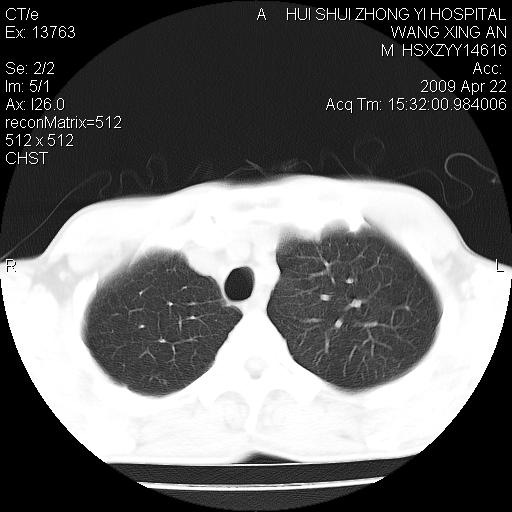

标题: CT19534:患者男、46岁咳嗽、胸痛半月。 [打印本页]

标题: CT19534:患者男、46岁咳嗽、胸痛半月。

1、右下肺中央型肺癌并右肺转移,右肺下叶不张。(肿块围绕右肺下叶支气管生长,致管腔闭塞右肺下叶不张;右肺有结节影)。

2、右侧胸腔积液。

3、右中上肺陈旧性肺结核(右肺见纤维化病灶及点状钙化)。

右肺中心型肺癌继发下叶不张,右下肺纤维灶,少量胸水。

1)右肺中间段支气管癌并右肺下叶肺不张。2)右肺上叶、两肺下叶背段感染性病变。3)右侧少量胸腔积液。